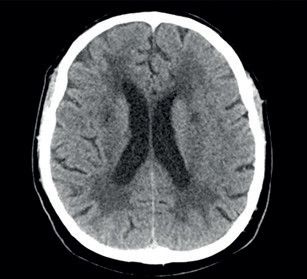

Potíže se začátkem roku 2019 opakovaly a přidala se k nim porucha časové orientace a pracovní paměti, pro což byl odeslán k akutnímu vyšetření v naší ambulanci. Pacient potíže negoval. Při neurologickém vyšetření byl klidný a orientovaný všemi modalitami. Působil zpomalenějším dojmem. Řeč byla plynulá, slovní projev měl normální. Nevykazoval známky kognitivní poruchy, neurotopický nález byl v normě. Vyšetření pomocí CT mozku prokázalo nespecifické změny bílé hmoty paraventrikulárně a subkortikálně (obr. 1). Vyšetření pomocí elektroencefalogramu (EEG) bylo normální. U pacienta byla zahájena léčba ASA v dávce 100 mg 1× denně a atorvastatinem v dávce 40 mg 1× denně. Dle MR mozku (únor 2019) byly přítomny změny bílé hmoty obou mozkových hemisfér charakteru splývající gliózy, která postihovala i pons. Dalším nálezem byly lakuny v bazálních gangliích, více vpravo (obr. 2). Dle radiologa obraz nejvíce připomínal Binswangerovu nemoc. Pacient se vyučil a v poslední době pracoval ve 12hodinovém směnném provozu jako řidič nákladního vozu na šachtě. Vojenskou prezenční službu absolvoval bez omezení. Úraz hlavy neprodělal. Nekouřil, denně vypil 1–2 piva. Dlouhodobě užíval alopurinol pro dnavou artropatii. Sledovaná interní a neurologická onemocnění negoval. V rodinné anamnéze stojí za zmínku náhle úmrtí otce v 59 letech (nalezen na chodníku), příčinu úmrtí neznal. Matka a synové jsou zdrávi. V rodině není zaznamenán výskyt neurologického nebo psychiatrického onemocnění. V březnu 2019 byl pacient přijat na naše oddělení pro smíšenou afázii, která v době přijetí trvala déle než 8 hodin. Další neurologický deficit přítomen nebyl. Vstupní CT mozku neprokázalo akutní změny v terénu splývajících hypodenzních změn v supratentoriální bílé hmotě oboustranně. CT angiografie (CTA) mozkových tepen ani neurosonologické vyšetření neprokázaly významnější patologii na extrakraniálních i intrakraniálních tepnách. Biochemické vyšetření séra potvrdilo hyperurikemii a hyperlipidemii, jiné abnormality přítomny nebyly. Glykemický profil byl normální. Vstupní hodnoty krevního tlaku byly mírně zvýšené (140–160/90–100 mm Hg), spontánně se během 24 hodin upravily do normotenzních hodnot. Vstupní EKG bylo normální a i monitorace EKG včetně Holterova monitorování EKG neodhalily srdeční arytmii. EEG bylo abnormní pro pomalou aktivitu theta a delta frontotemporálně vpravo. Sérologický test na syfilis, onkomarkery, onkoneurální protilátky a laboratorní testy na vaskulitidy byly negativní. Během 48 hodin se fatická porucha plně upravila. Pacient sděloval, že se cítí dobře a nemá žádné potíže. Na vlastní žádost (negativní revers) byl propuštěn do domácí péče. K vyšetření trombofilních stavů se nedostavil. Po opakovaném odložení ze strany pacienta bylo v dubnu 2019 doplněno vyšetření mozkomíšního moku z lumbální punkce. Zjištěna lehce zvýšená hodnota bílkoviny (0,68 g/l) a hraniční lymfocytární pleocytóza s přítomností výraznější aktivity v monocytární řadě. Cytologický nález byl v normě. Absence známek intratekální oligoklonální syntézy imunogobulinů G, A, M (IgG, IgA, IgM) a volných lehkých řetězců (FLC) kappa/lambda nesvědčily pro demyelinizační onemocnění typu sclerosis multiplex. Absence protilátek IgG proti aquaporinu 4 v krvi vylučovaly neuromyelitis optica. Koncentrace tau proteinu byla normální. Protein 14‑3‑3 byl negativní. Neuroborelióza byla vyloučena. S odstupem bylo provedeno kontrolní vyšetření mozku pomocí MR, ve srovnání s předchozím vyšetřením však neodhalilo nové změny. MR angiografie (MRA) mozkových tepen zobrazovala normální nález na intrakraniálních tepnách. Další vyšetření včetně genetického pacient neakceptoval.